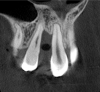

Tomographic images revealed a large tridimensional defect, with vertical and horizontal loss of bone extending to the apical third of teeth Nos. 6 and 8. Additionally, a buccal bone dehiscence was evident on tooth No. 5, and thin labial plates secondary to the orthodontic movement were present in several areas (Figure 3 and Figure 4).

Fig 4. Tomographic images revealed a tridimensional defect extending to the apical third of teeth Nos. 6 and 8, a buccal bone dehiscence on tooth No. 5, and associated thin labial plates.

Figure 4